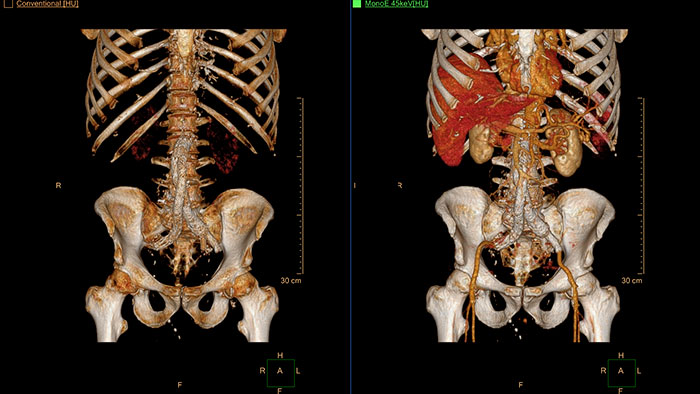

Endovascular stent placement

CT Advanced Vessel Analysis (AVA) Stent Planning includes multiple preset and user-defined options to gain detailed information for use in stent planning.

Benefits